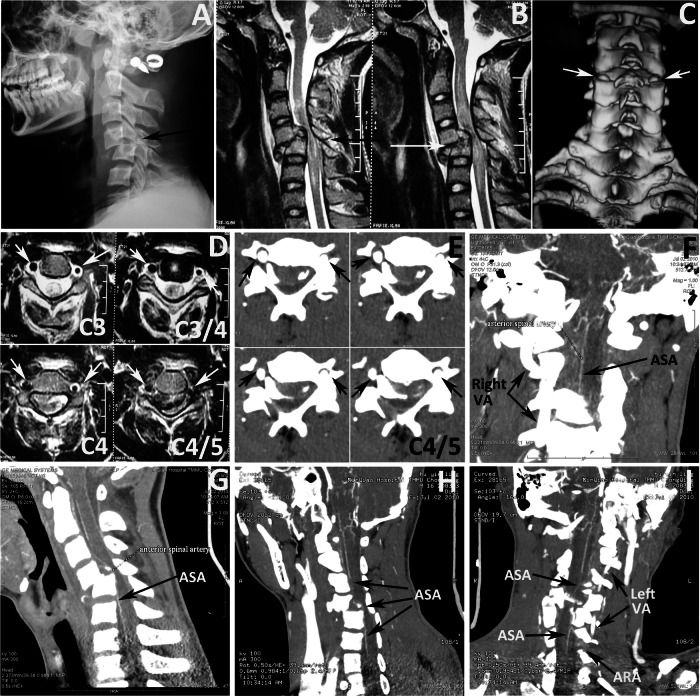

The VA was identified by axial MRI, axial CTA, coronal CTA, and oblique CTA images. VA occlusion was diagnosed on axial MRIs with asymmetrical flow void and/or absence of flow void in either of both Vas [2, 7]. The absence of VA images in axial CTA, coronal CTA, and oblique CTA was also identified as VA occlusion (Figs. 2D–I and 3D–I). The diagnosis of VA occlusion was achieved by consensus between 2 neuroradiologists to avoid clinical subjectivity.

Fig. 2. Illustrative case of ASA visualization without VA occlusion (16 years old case).

A Lateral radiograph showing C5 fracture and dislocation. B Sagittal T2-weighted MRI showing cord hyperintensity at C3–C6 and C5 fracture (arrow). C Three-dimension CT reconstruction image showing the bilateral C4/5 facet dislocation (arrows). D T2 axial MRI showing bilateral intact VA at C3 to C4/5 (arrows). E Axial CTA showing bilateral intact VA at C4/5 (black arrows). F coronal view of CTA showing no ASA occlusion (black arrow) and right intact VA (black arrows). Sagittal (G) and oblique (H) views of CTA showing no ASA occlusion (black arrows). I oblique views of CTA showing no ASA occlusion (black arrows), intact VA (black arrows) and ARA (black arrow).

Fig. 3. Illustrative case of ASA visualization with VA unilateral occlusion (case 3).

A Sagittal CT image showing C4/5 dislocation (arrow). B Three-dimension CT reconstruction images showing right C4/5 facet dislocation (arrow). C Sagittal T2-weighted MRI showing cord hyperintensity at C3–C6 and C4/5 dislocation. D Axial CTA showing left intact VA (white arrows) and right occluded VA (black arrows) at C3/4 to C4/5. E Axial T2- weighted MRI showing left intact VA (white arrows) and right occluded VA (black arrows) at C3–C6. F Coronal view of CTA showing left intact VA (white arrows) and right occluded VA (black arrows). Coronal (G) and sagittal (H) views of CTA showing no ASA occlusion (arrows). I Oblique views of CTA showing no ASA occlusion (arrows), intact VA (arrows) and ARA (arrow).

In all 21 patients with cervical facet dislocation, both the VA and ASA were successfully visualized. The course of the ASA, extending from C1 to C7, was clearly visualized in sagittal, coronal, and transverse views. The ASA ran along the entire length of the anterior surface of the spinal cord. The ARA was also visualized in CTA for all cases. The VA and its occlusion were visualized in axial MRI, axial CTA, coronal CTA, and oblique CTA images (Figs. 2D–I and 3D–I).

The occurrence of ASA occlusion

In all 21 patients with cervical dislocation, no ASA occlusion was found in the absence of VA occlusion (16 patients) (Fig. 2A–I), nor was it found in cases with VA unilateral occlusion (5 patients) (Fig. 3A–I).